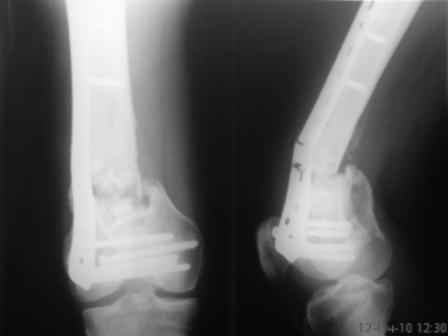

Больной, 30 лет, высокоэнергетическая травма 6 мес назад (базальный перелом шейки бедра + перелом дистального метаэпифиза бедра на той же ноге по типу 33-С2). Практически сразу же был произведен МОС шейки системой DHS (Synthes), через две недели - МОС дист.отдела бедра системой LISS (Synthes)плюс костная пластика с крыла подзвдошной кости.

На сегодняшний день наступил перелом пластины, укорочение бедра 2 см. Перелом шейки клинически и рентгенологически сросся. Больной астеничен, немного анемичен. Рентгенограммы прилагаются.